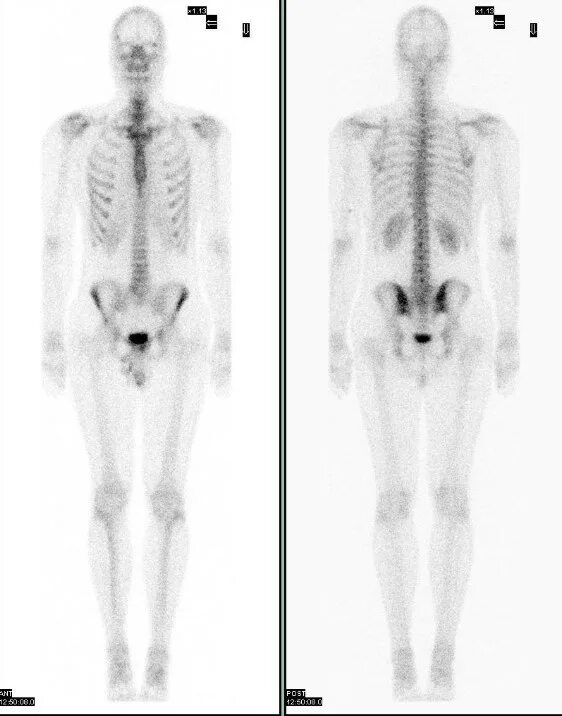

Как называется исследование костей